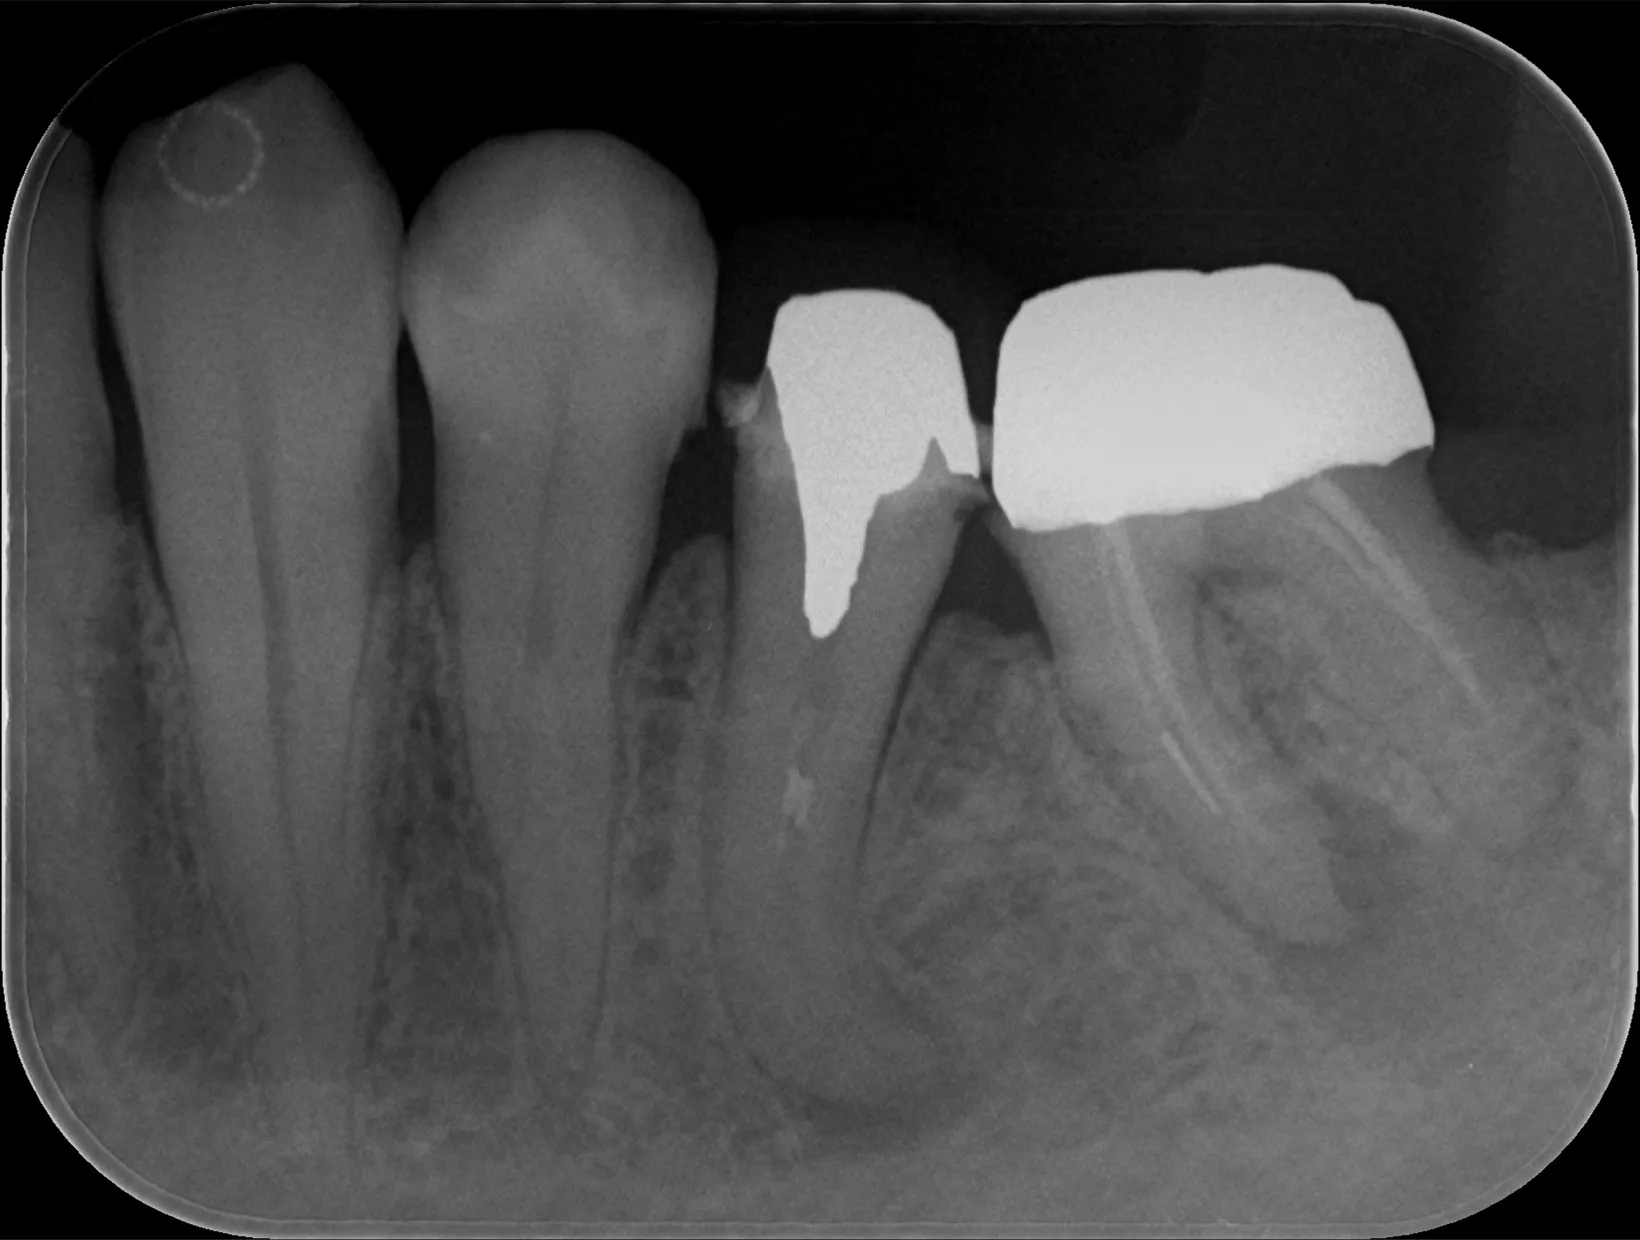

レントゲン画像

治療後

根管治療が終わった時のレントゲン画像です。治療前には写っていなかった白い線状の詰め物を根管に詰めて確認を取っているところです。

右の歯は治療の手を付けていない状態です。

詰め物はしたものの根尖部にある黒い像は変わらずあります。

これはいいのか?と疑問に思うかもしれません。

結論から言うと、問題ありません。

なぜよいのかというと、黒く写っている部分は骨が溶けていた部分です。

膿などの感染物が除去されたとしても骨がすぐに治るということはありません。

すぐ骨が再生するのであれば骨折した場合には全治3か月などと時間はかかりませんよね。

今回根管治療にかかった期間は約2週間です。

感染が除去されても2週間では骨が改善しないため黒い影が残っていても全く問題ないのです。

根管治療は歯の中のかなり細い管での操作になるため、ただでさえ治療中見えにくいのに、根っこが湾曲しているとなると根の先は全く見えません。

そのため最後には必ずレントゲンで問題なく治療されたのか確認をしています。

彎曲度合いが強すぎると器具が入っていかなかったり途中で器具が折れてしまうなんてことも出てきます。